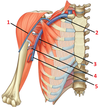

1? 2?

1: Levator scapulae muscle

2: Rhomboid major and minor muscles

1? 2?

1: Teres major muscle

2: Latissimus dorsi muscle